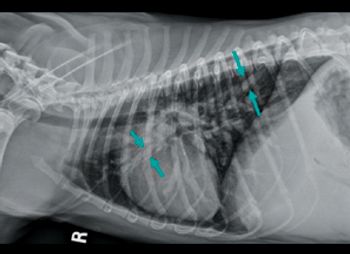

Cats presenting with pleural effusion are nearly always in respiratory distress, ranging from an increased respiratory rate and effort to open mouth breathing. In the latter situations, therapeutic intervention must be initiated quickly to prevent respiratory arrest. The therapeutic intervention also provides your first diagnostic test.

Respiratory abnormalities are relatively common in cats, who may suffer from a wide range of disease processes. An initial triage step in the management of a dyspnic cat is to determine whether the dyspnea is cardiogenic or due to extracardiac (primary pulmonary) disease. This task is in no way a simple one, as cats often have non-specific history and physical examination abnormalities.